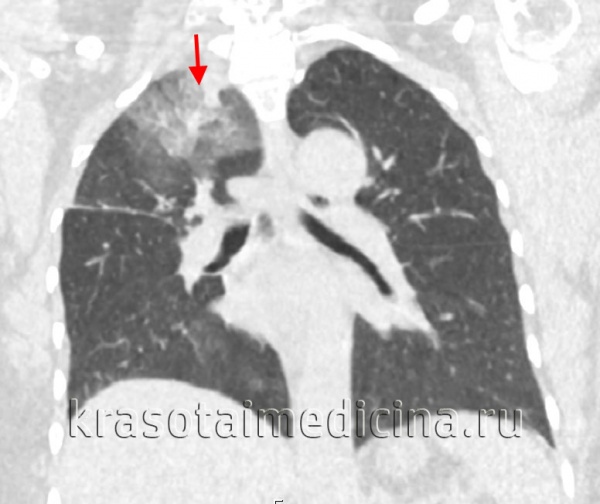

Облаковидный инфильтрат в верхней доле правого

легкого [обзорный снимок (а) + томограмма (б)]. В

верхней доле правого легкого определяется 2

фокуса .

Рентгенологически, как это установил Г. Р. Рубинштейн (1948), облаковидный инфильтрат выглядит как неравномерное затемнение без четких границ. Процесс распространен на один или несколько сегментов, чаще верхних долей легких. По своей теневой картине он напоминает неспецифическую очаговую пневмонию, но отличается от нее рядом клинических признаков, стойкостью рентгенологических изменений, тенденцией к распаду и образованию каверны.

Если облаковидный инфильтрат локализуется у главной или дополнительной междолевой борозды, а иногда связан с корнем легкого, то его определяют как перисциссурит, краевой инфильтрат или треугольник Сержана. Вершина его обращена к корню легкого, а основание — кнаружи. Верхняя его граница расплывчата и переходит без резких очертаний в малоизмененную легочную ткань, нижняя — соответствует междолевой плевре. Топографию и структуру облаковидного инфильтрата или перисциссурита, которые чаще всего располагаются в верхней доле правого легкого, удается уточнить при послойном исследовании легких. При этом на томограмме на фоне инфильтративных изменений выявляются тени отдельных или множественных более плотных очагов, тяжистый рисунок уплотненной перибронхиалыюй и периваскулярной межуточной ткани, полости деструкции.

Облаковидный инфильтрат рентгенологически выглядит как нежная

слабоинтенсивная гомогенная тень с нечеткими, размытыми контурами с распространением на один или несколько сегментов, чаще верхних долей легких. По своей теневой картине похож на неспецифическую пневмонию, но отличается от нее рядом клинических признаков, стойкостью рентгенологических изменений, тенденцией к распаду и образованию каверны.

Диаметр инфильтратов достигает 3 – 5 см, без четких контуров, часто с полоcтью деструкции, в окружающей легочной ткани – очаговые изменения.

Если облаковидный инфильтрат локализуется у главной или дополнительной междолевой щели и связан с корнем легкого, то его определяют как краевой инфильтрат или перисциссурит .

Чаще всего располагается в верхней доле правого легкого. Вершина его обращена к корню легкого, а основание — к грудной стенке.

Верхняя его граница расплывчата и переходит без резких очертаний в малоизмененную легочную ткань, нижняя — четкая, соответствует междолевой плевре.